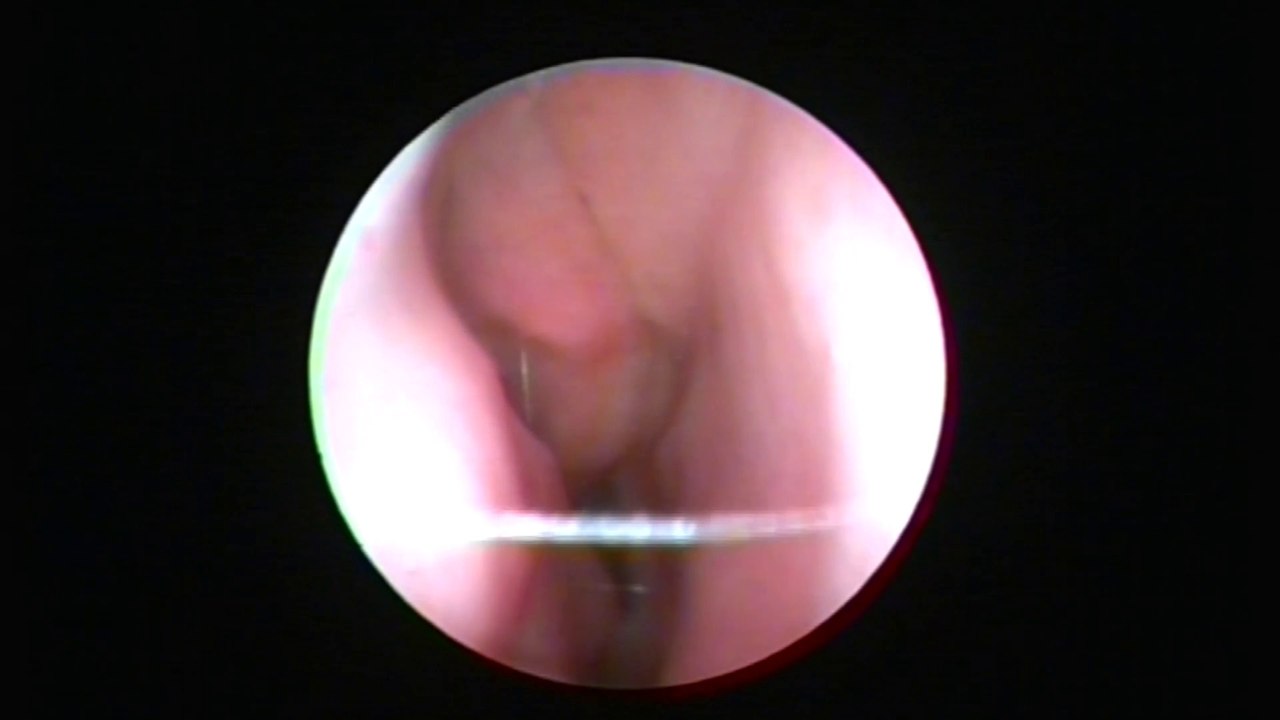

Başarılı Sinüzit Tedavisi ve Sinüzit Ameliyatı

https://atillasengor.net/s/sinuzit-ameliyati-endoskopik-sinus-cerrahisi <br /> <br />Dr. Erhun Şerbetci başarılı bir sinüzit ameliyatı için gereken koşulları anlatıyor.